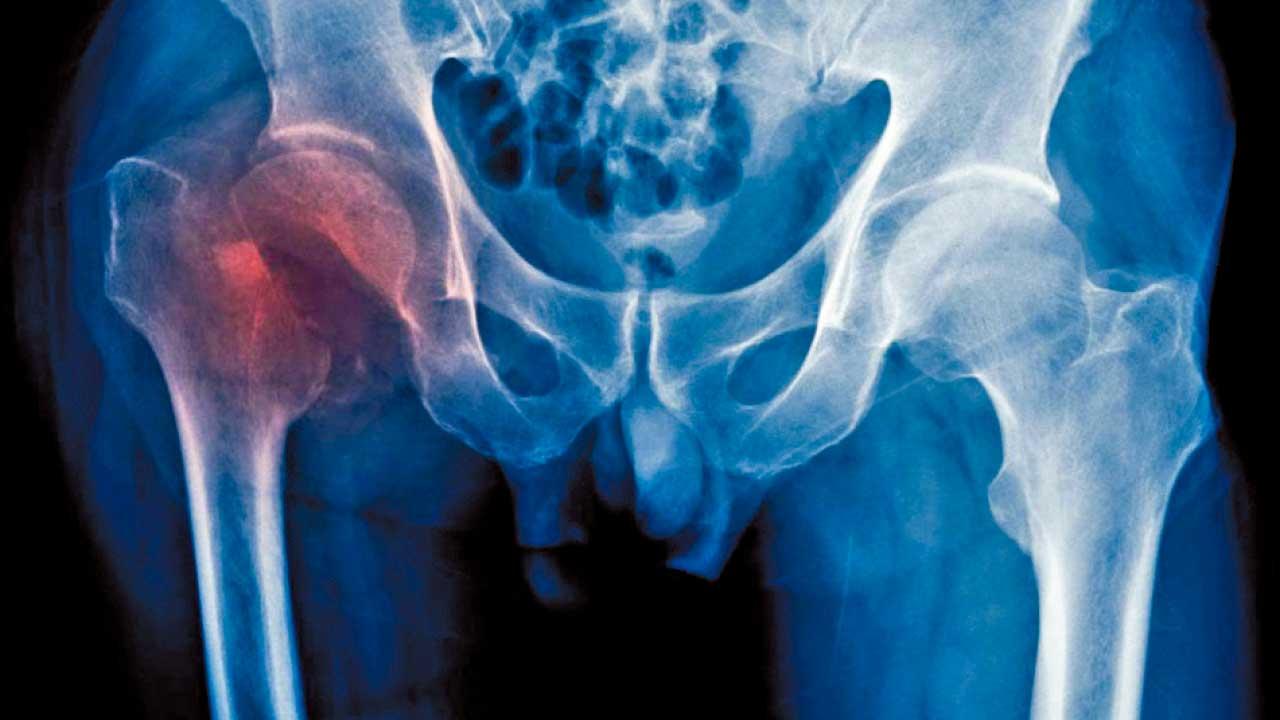

根據國際骨質疏鬆基金會統計數字,全球50歲以上的人當中,每3位女性或每5位男性當中就有一位遇上脆性骨折。香港醫院管理局在2014年的統計顯示,脆性骨折的病例比同年心肌梗塞或中風的病例高兩至七成。其中髖部骨折的後遺症最為嚴重,患者可能會長期疼痛到無法走路,並終身需要輪椅代步。另有不同海外研究指出,多達五分之一的病人會在髖部骨折後一年內死亡;只有三分之一髖部骨折的病人可在康復過程中回復昔日的活動和自理能力。